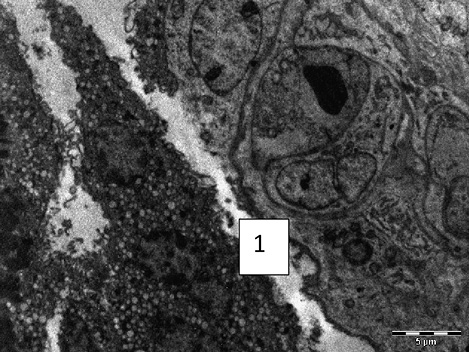

Электронно-микроскопическое исследование плаценты при ПОНРП выявило следующие морфофункциональные особенности: цитоплазма синцитиотрофобласта визуализировалась ячеистого вида из-за резкого расширения просветов канальцев эндоплазматической сети; в местах разрушения канальцев были видны очаги локальной деструкции; митохондрии — набухшие, отмечалась деструкция крист, просветление, а порой опустошение митохондриального матрикса; ядра визуализировались неправильной формы, деформированые; хроматин гомогенного вида; микроворсинки распределялись равномерно, но строма ворсин была разрыхлена, отечная, в строме просматривалось обилие мононуклеаров. Присутствовало нарушение межклеточных контактов между децидуальными клетками. Большинство просмотренных сосудов резко полнокровны, в просветах видны сладжированные эритроциты. В просвете некоторых сосудов наряду с эритроцитами выявляются скопления тромбоцитов, нити фибрина, адгезия тромбоцитов к эндотелию; также визуализировалась межклеточная локализация фибрина. В некоторых ворсинах определяются массивные кровоизлияния с пропитыванием стромы (Рисунки 1, 2, 3, 4). Таким образом, при изучении морфологической архитектуры ткани плацент при ПОНРП четко прослеживается морфофункциональная характеристика плацентарной недостаточности и наличие ультраструктурных характеристик ее декомпенсации.

Рисунок 1. Фрагмент синцитиотрофобласта при ПОНРП. Выраженная вакуолизация цитоплазмы синцитиртрофобласта (1) с формированием очагов деструкции. (Роженица К., 29 л.). Ув. х3500

Figure 1. Fragment of syncytiotrophoblast in PONRP. Pronounced vacuolization of syncytiotrophoblast cytoplasm (1) with formation of foci of destruction. (Mother K., 29 years old). Magnification x3500